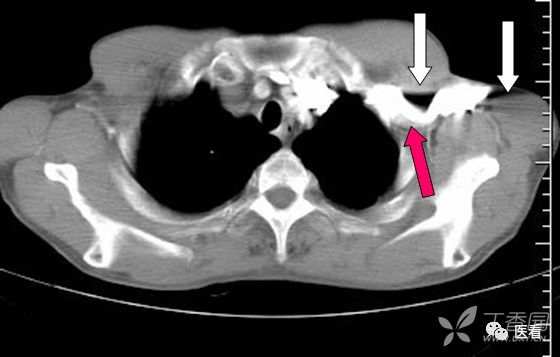

6 团注高浓度碘对比剂(红箭头)形成的伪影(白箭头)

注入造影剂的方法有快速静脉滴注法和静脉团注法(bolus injection)。静脉滴注法以20ml ~30ml/min速率滴注造影剂,待开始扫描时,造影剂已分布于动脉期、静脉期和平衡期,不能进行分期扫描,现已基本不再使用。目前主要采用静脉团注法中的动态团注CT增强扫描(Dynamic bolus contrast-enhanced scan)。动态团注CT增强扫描又称动态CT增强扫描(Dynamic enhancement CT scan),是一种对注射造影剂速度、扫描时间进行程序控制的增强CT检查技术。检查前根据需要预先设定扫描层面、扫描次数、间隔时间和床动速度等参数;使用高压注射器,短时间内快速将造影剂团注(bolus)入静脉。注射速率一般为2~3ml/s,根据需要,注射速率可增至5ml/s,目前文献报告最大注射速率为10ml/s。造影剂总量80~180ml。

对于团注高密度碘对比剂,可以采用足端→头端扫描而规避。